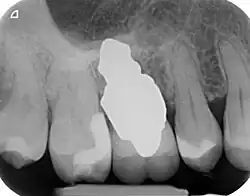

Recovery time is very fast as neither soft nor hard tissue is traumatised. Typically, even the day after implant placement there is no swelling, bruising or pain. After 8–12 weeks' healing period, the final crown may be fitted by a family dentist.

- Esthetic: a ceramic RAI closely resembles a natural tooth in colour. Thus there is no discolouration through the gums, as is commonly seen with titanium implants.

- No drilling or surgery, or bone augmentation, is necessary. The patient never needs a sinus lift. There is no additional bone loss, in contrast to a conventional implant where bone must be drilled. No antibiotics are necessary.

- Extremely low risk of peri-implantitis: a conventional implant has a screw winding which is prone to peri-implantitis if it is exposed to the mouth environment. A RAI has none of these problems. Similarly, as it is a single piece implant, there are no gaps which can be infected.

- Immediate: a RAI is placed into a tooth socket immediately or the next day after tooth removal. Injury to neighbouring roots, nerves or sinus is impossible.